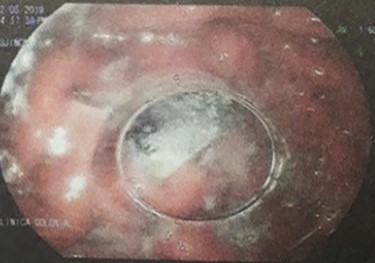

On clinical examination, a dehydrated and tachycardic (112 bpm) patient was encountered, she had diffuse pain in her lower abdomen without tenderness. After reanimation, an abdominal X-ray found two metal bodies in the bowel (Fig. 1); therefore, a computed tomography (CT) was requested, which revealed two metal foreign bodies, (razor blades) one in the stomach and one in the cecum without pneumoperitoneum (Fig. 2). As the patient did not have any tenderness, an upper endoscopy and colonoscopy were planned. During the upper endoscopy, the razor blade was detected in the antrum and was embedded in the mucosa (Fig. 3). After several failed attempts to remove the foreign object, the procedure was interrupted due to a risk of inadvertent perforation, and surgery was decided.

Upper endoscopy, the razor blade is seen embedded in the mucosa.